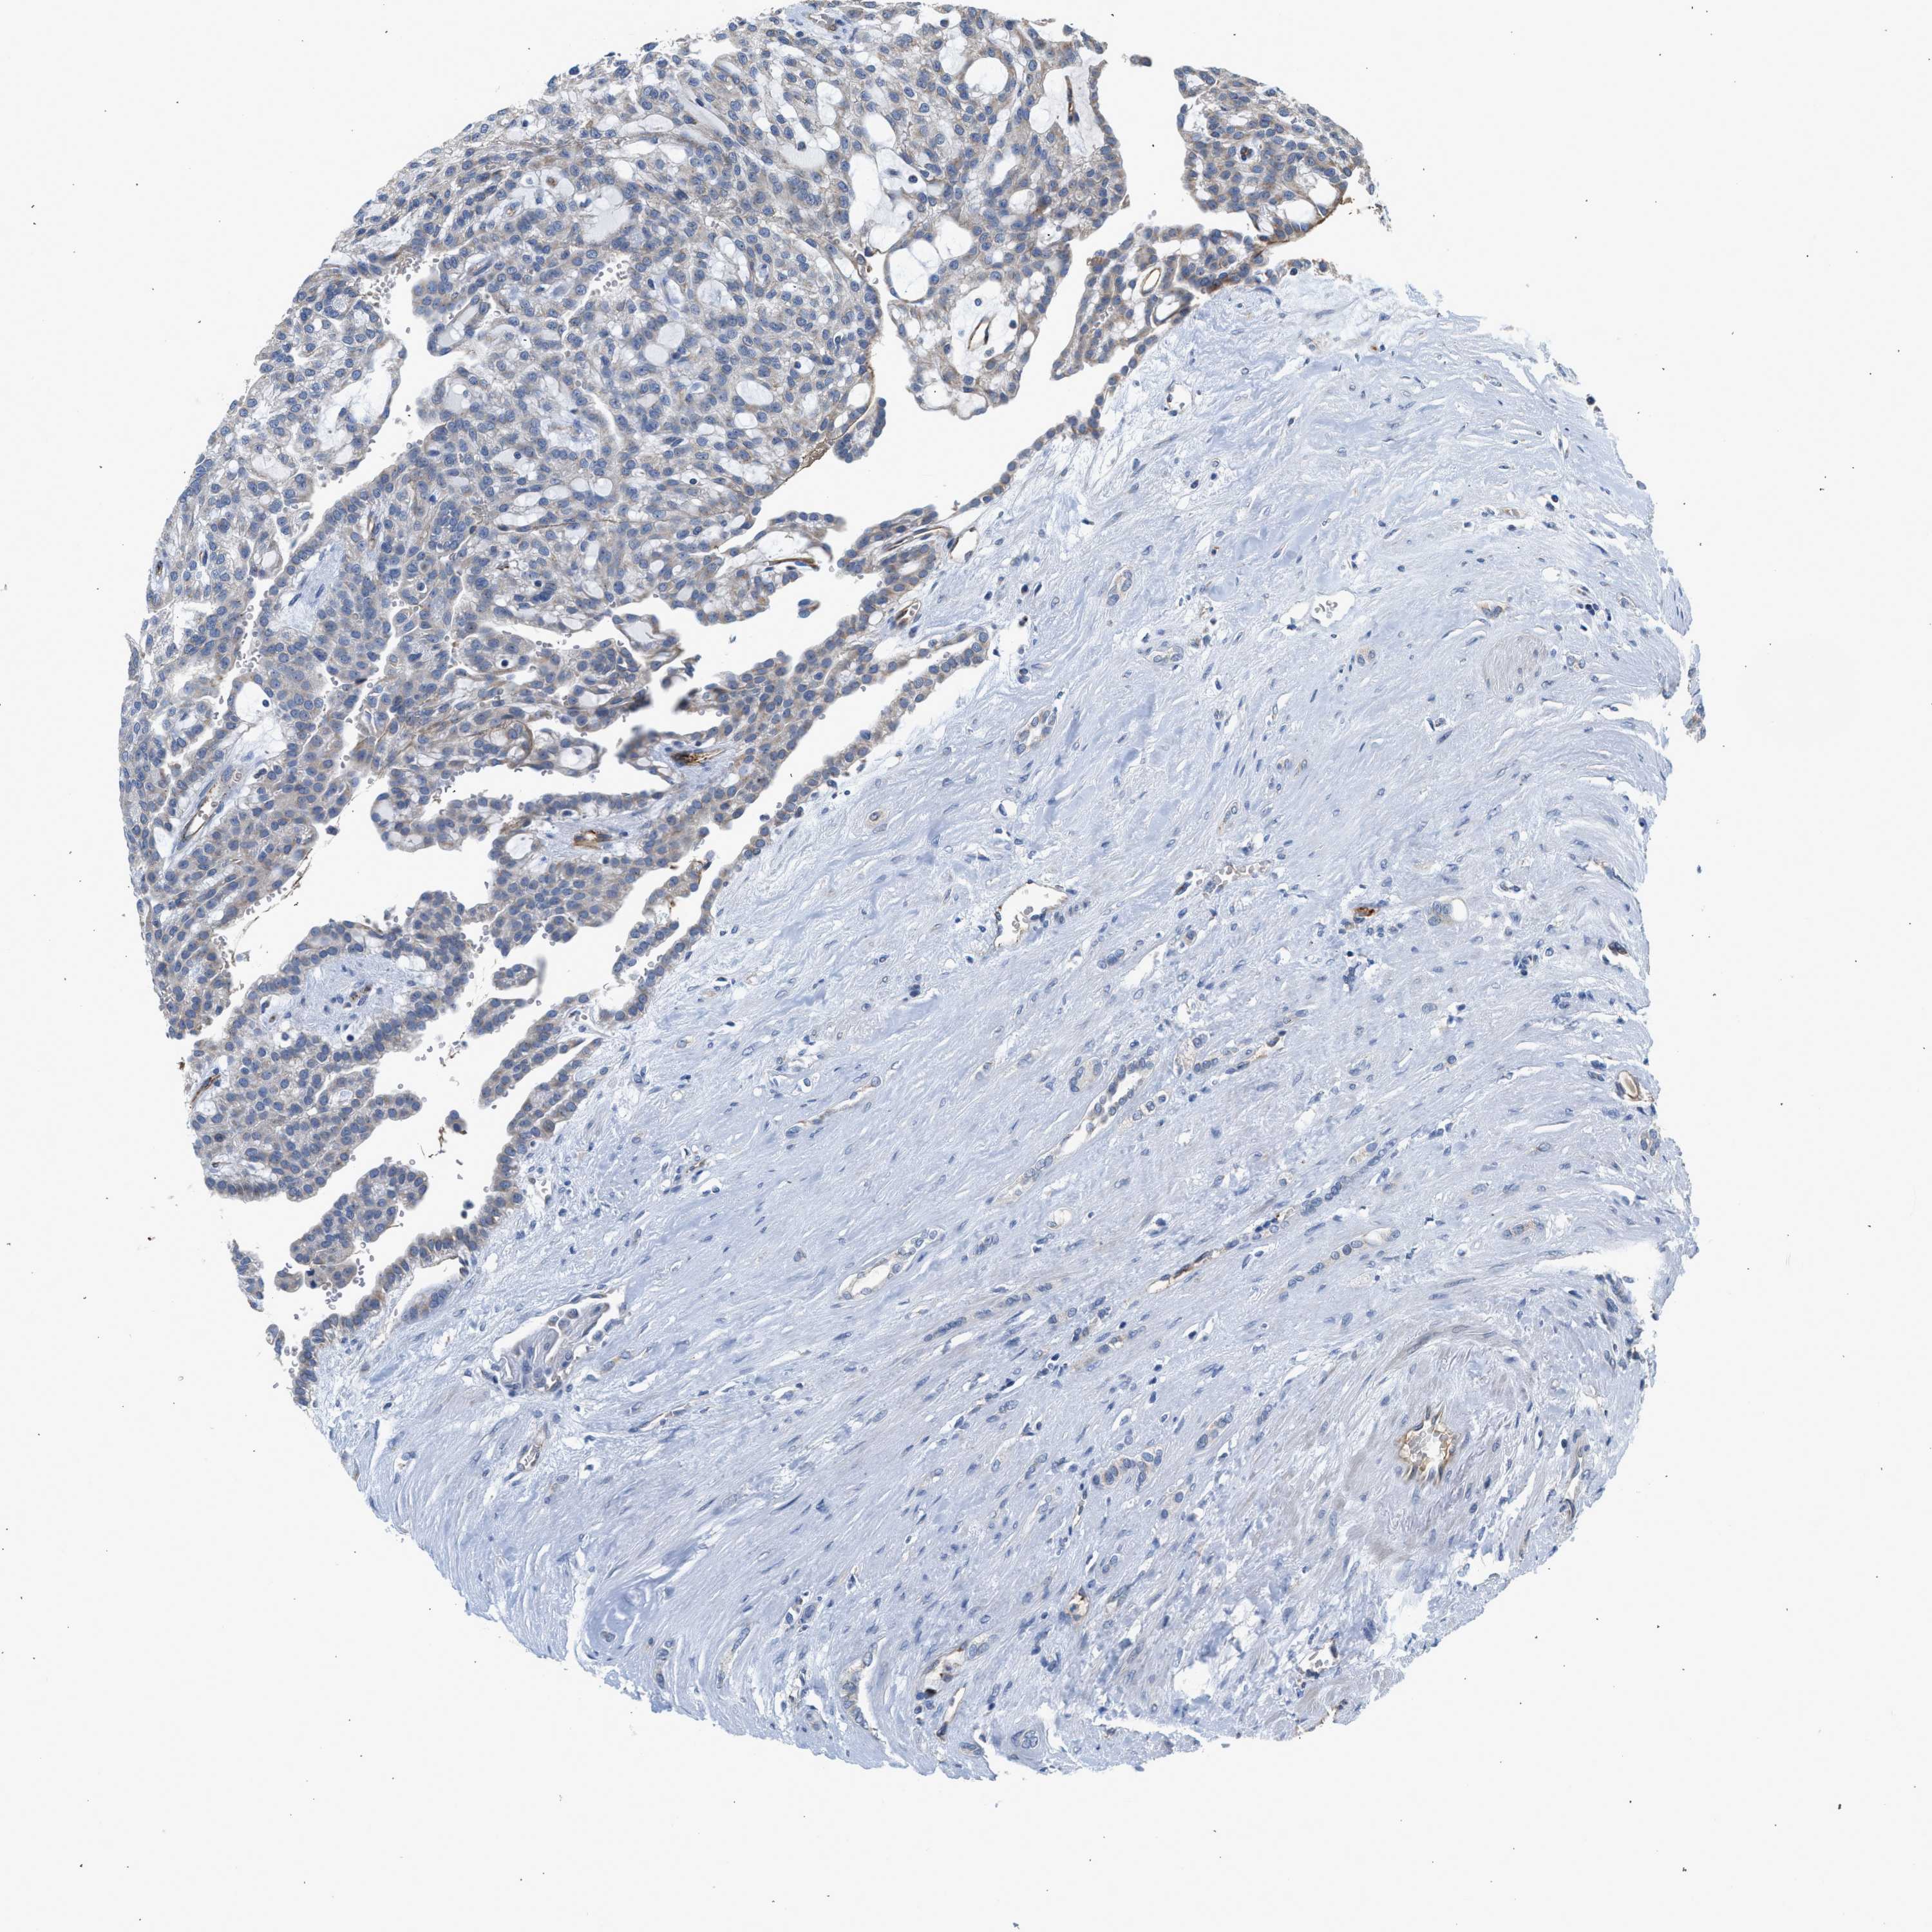

KIDNEY RENAL PAPILLARY CELL CARCINOMA (TCGA) - Interactive survival scatter ploti

The Survival Scatter plot shows the clinical status (i.e. dead or alive) for all individuals in the patient cohort, based on the same data that underlies the corresponding Kaplan-Meier plots. Patients that are alive at last time for follow-up are shown in blue and patients who have died during the study are shown in red.

The x-axis shows the expression levels (FPKM) of the investigated gene in the tumor tissue at the time of diagnosis. The y-axis shows the follow-up time after diagnosis (years). Both axes are complimented with kernel density curves demonstrating the data density over the axes. The top density plot shows the expression levels (FPKM) distribution among dead (red) and alive patients (blue). The right density plot shows the data density of the survived years of dead patients with high and low expression levels respectively, stratified using the cutoff indicated by the vertical dashed line through the Survival Scatter plot. This cutoff is automatically defined based on the FPKM cutoff that minimizes the p-score. The cutoff can be changed by dragging the vertical line or by entering a cutoff value in the square labeled "Current cut-off".

Under the Survival Scatter plot the p-score landscape (black curve; left axis) is shown together with dead median separation (red curve; right axis). Dead median separation is the difference in median mRNA expression between patients who have died with high and low expression, respectively. It is calculated as follows: median FPKM expression of dead patients with high expression - median FPKM expression of dead patients with low expression. This is intended to aid the user in visually exploring custom cutoffs and the associated p-scores and dead median separation.

Individual patient data is displayed and can be filtered by clicking on one or more of the category buttons on the top of the page. Categories describing expression level and patient information include: high, low, alive, dead, female, male and tumor stages. The scale of the x-axis can be toggled between linear and log-scale by clicking on the "x log" button. Mouse-over function shows TCGA ID, patient information and mRNA expression (FPKM) for each patient.

& Survival analysisi

Kaplan-Meier plots summarize results from analysis of correlation between mRNA expression level and patient survival. Patients were divided based on level of expression into one of the two groups "low" (under cut off) or "high" (over cut off). X-axis shows time for survival (years) and y-axis shows the probability of survival, where 1.0 corresponds to 100 percent.

PIM1 is not prognostic in Kidney Renal Papillary Cell Carcinoma (TCGA)